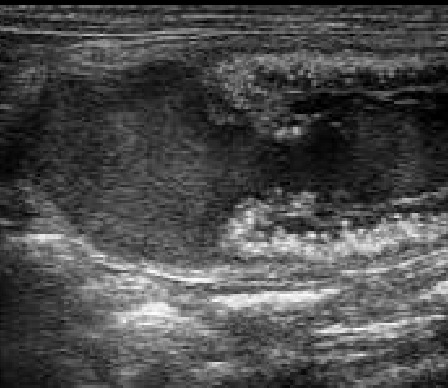

¿Qué método confirma el diagnóstico de DPPNI?

A

Ecografía: Puede mostrar un hematoma retroplacentario. 📷